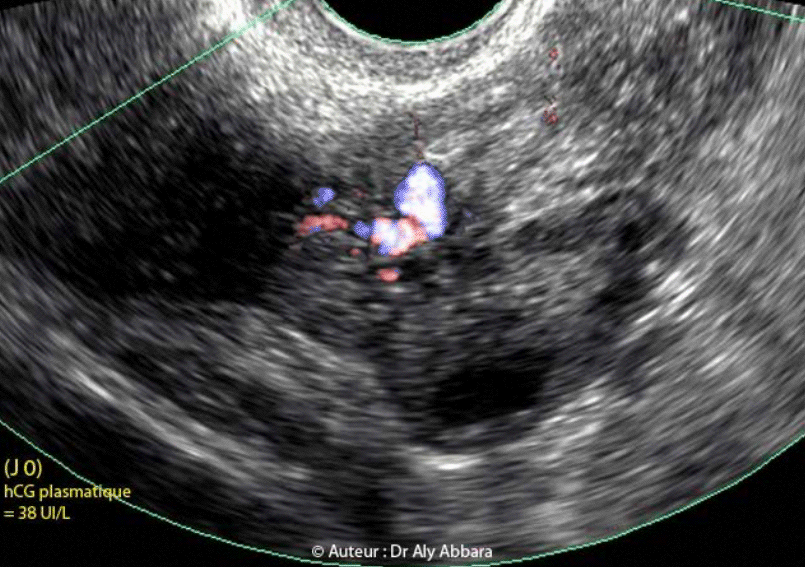

• A (7 SA et 4 jours) : légère métrorragie ; discrète douleur spontanée et intermittente, pelvienne latéralisée à gauche ; examen clinique normal ; l'échographie montre une image latéro-ovarienne gauche mesurant (7 x 7 x 8 mm) de diamètre faisant évoquer, par son aspect vésiculaire entouré par une couronne échogène, le diagnostic de sac gestationnel ectopique.

Ce jour, le dosage de β-hCG plasmatique était égal à (38 UI/L).